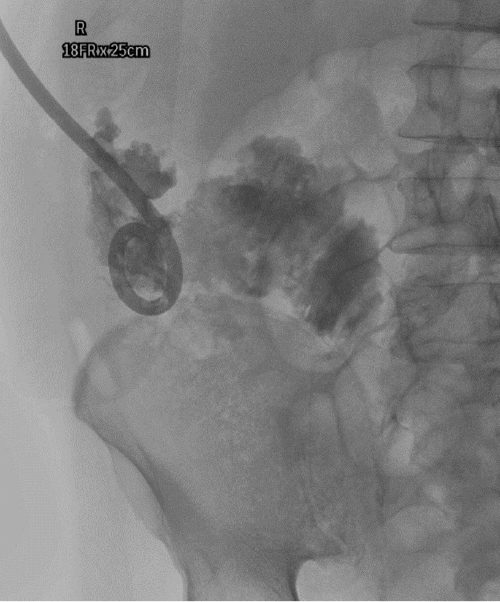

On arrival, he was afebrile but exhibited tachycardia, tachypnea, and hypotension. Shortly after his arrival, he suffered cardiac arrest. Cardiopulmonary resuscitation (CPR) was initiated, with return of spontaneous circulation (ROSC) achieved after six minutes. The patient was subsequently intubated and mechanically ventilated; a comprehensive physical examination was deferred due to his critical instability. Initial laboratory investigations were consistent with severe metabolic acidosis and sepsis. An emergent computed tomography (CT) scan of the abdomen and pelvis revealed a massive 27.2 × 14.2 × 16.1 cm rim-enhancing retroperitoneal fluid collection, consistent with an abscess, which extended inferiorly along the right iliopsoas muscle to the level of the right thigh (Figure 1). Concurrently, a CT of the chest identified left-sided subsegmental pulmonary emboli (PE). Although the appendix was poorly visualized on the initial CT, perforated appendicitis could not be excluded as a potential etiology.

Figure 1. Initial CT Demonstrating Massive Retroperitoneal Abscess. Published with Permission

(A) Coronal and (B) axial views from a contrast-enhanced CT scan on presentation. The images reveal a massive, 27.2 × 14.2 × 16.1 cm, multiloculated, rim-enhancing fluid collection in the right retroperitoneum, extending along the iliopsoas musculature and through the femoral canal into the thigh